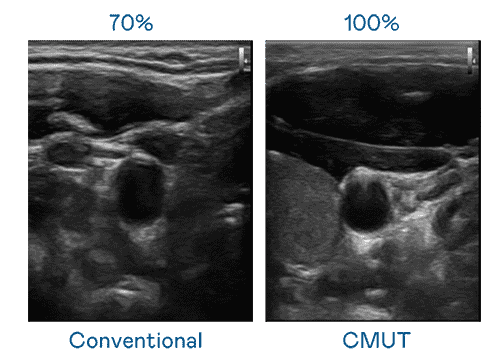

CMUT 技术是一种用电容式微机电元件来产生超音波讯号的技术。。。与传统 PZT 压电式技术相比,,,CMUT 频宽增加 30%,,,,更宽频的超音波讯号让影像解析度大幅提升,,,是实现高影像品质医疗超音波扫描、、、、促进精准医疗发展的关键技术。。。

大频宽带来超清晰影像

超音波影像的解析度高低,,,,首先取决于探头能发出的讯号频宽。。2121非凡 CMUT 可提供高清晰的超音波讯号,,提供高频宽、、、、高灵敏度、、、影像纹理细节更高的超音波影像,,,,协助医护人员缩短影像判读时间及利用精准的医疗影像进行诊断。。